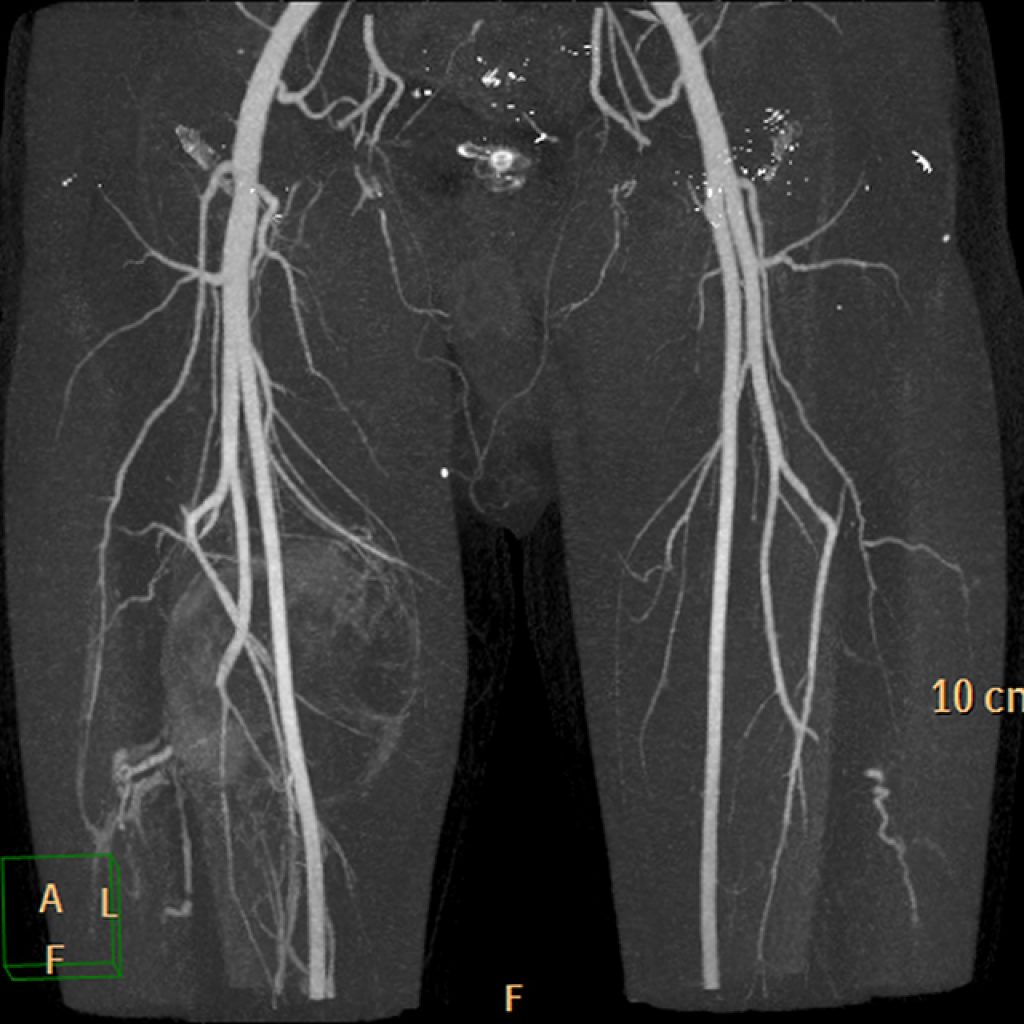

- Ангиография. В этом методе в сосуды нижних конечностей вводится контрастное вещество, после чего проводится рентгенографическое исследование. Это позволяет врачу точно определить участки нарушения кровообращения и выбрать подходящий метод лечения.

- Допплерография. Исследование проблемных участков на ногах выполняется с помощью ультразвукового оборудования, что дает возможность точно оценить состояние сосудов и выявить очаги проблемы.

Допплерография и ангиография являются наиболее надежными методами для определения мест поражения сосудов. Однако для выявления причин проблемы необходимо провести комплексное исследование, чтобы понять, что стало причиной появления трофических язв на нижних конечностях.